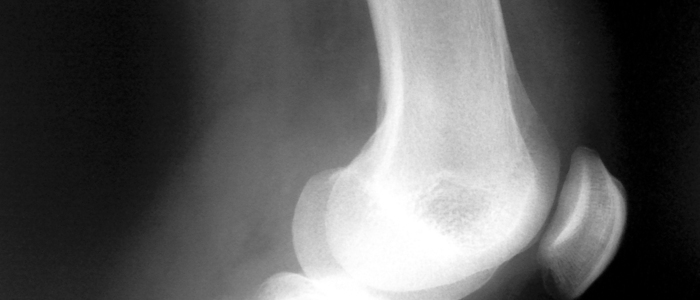

Mezi klouby, které nejčastěji křupou nebo lupou, patří ty v kolenou, klouby na prstech rukou, páteř, krk, boky a kotníky.  Častokrát tyto zvuky neznačí žádný problém. Pokud vás ale místo, odkud lupání vychází, začne svědit, je rozehřáté nebo dokonce bolí, stojí za to navštívit doktora.

Aby se právě klouby mohly snadno pohybovat a otáčet, tělo produkuje tekutinu nazývanou synoviální tekutina nebo také kloubní maz, která působí jako lubrikant. Díky tomu v kloubech nedře kost o kost a jsou umožňuje tělu být pohyblivé do všech směrů, které potřebujete.

Právě kloubní maz obsahuje i směs různých plynů. Při pohybu se pak tyto plyny uvolňují ve formě mikrobublin a klouby lupou. A přesně to pak slyšíte a cítíte lupnutí v kloubech.

Občas se také ale může stát, že šlacha, která kloub obklopuje, se při pohybu lehce posune a při návratu na původní místo lupne. Pokud trpíte artritidou, křupání nebo lupání v kloubech může být také způsobeno nedostatkem kloubního mazu, kdy kosti začínají dřít jedna o druhou.